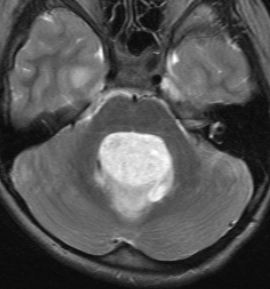

MR画像の特徴について(T2で白い)

pilocerebel-2pilocerebel-1pilocerebel-3

7歳の子の小脳虫部腫瘍です。左と中央のMRIをみると一見,髄芽腫に見えます。でもこれは毛様細胞性星細胞腫で,手術で全部取れて,後遺症もなく治りました(右側)。inverted T2(左側のCISS)では黒く(低信号)に写って小脳との境界が明瞭です。

T1強調画像のガドリニウム増強(左)ではわかりませんが,右のT2強調画像で腫瘍部分がとても白く(強い高信号)に写っているのが,最大の特徴です。多くの場合,T2強調画像で毛様細胞性星細胞腫の診断がつきます。このようなT2でかなり強い高信号になるものは毛様粘液性星細胞腫の成分を含むことが多いです。